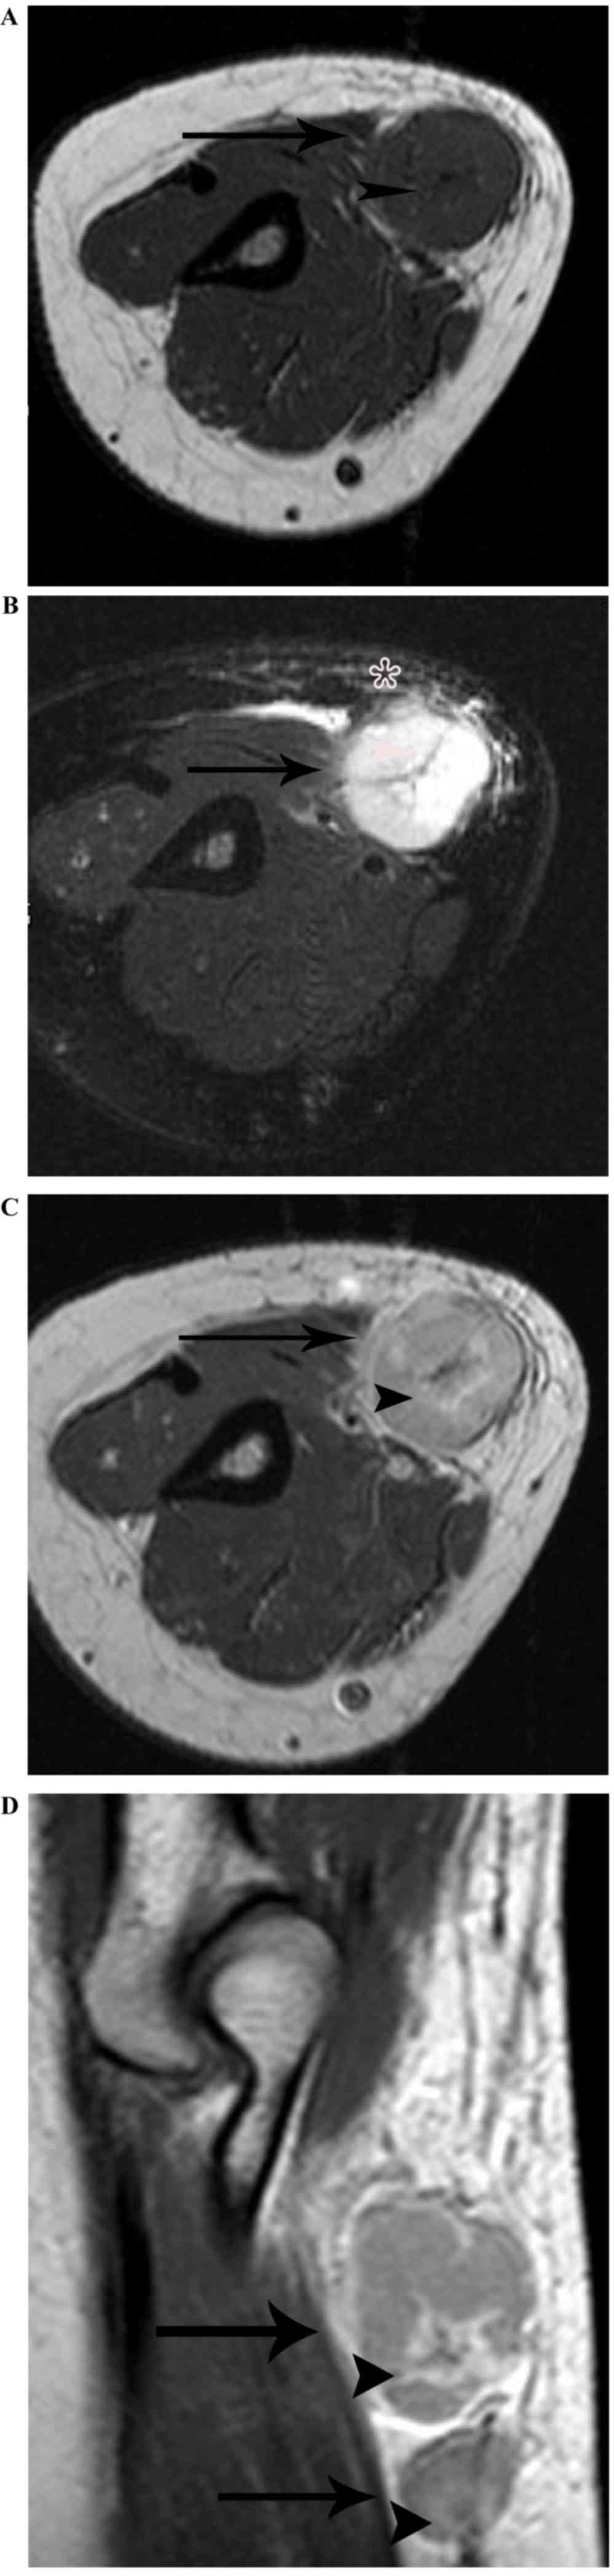

On the MRI scans, all the 14 nodes identified were homogeneously or heterogeneously isointense to muscle or with slightly increased intensity compared with that of muscle on T1WI, and homogeneously or heterogeneously hyperintense on fat-suppressed T2WI. Subsequent to enhancement, 8 of the 14 nodes displayed moderately homogeneous enhancement with no necrotic areas (Fig. 2) and 2 of the 14 nodes demonstrated marked heterogeneous enhancement with no enhancement of the necrotic central areas, which demonstrated patchy hypointense on T1WI and patchy hyperintense on T2WI in the center (Fig. 3A-C). Another 2 of the 14 nodes exhibited heterogeneous enhancement with marked enhancement of the astral hypointense area on T1WI and T2WI (Fig. 4A-C), and the other 2 exhibited heterogeneous enhancement with marginal petaloid enhancement of the astral hypointense area, namely the ‘rose flower’ sign (Fig. 5A-C). In addition, all 10 cases demonstrated general subcutaneous edema in the vicinity of the nodes.

Figure 5.

Lymphadenopathy in a 37-year-old woman with cat-scratch disease at the late stage in the right elbow. (A) The node (arrow) demonstrates heterogeneous isointensity to muscle with astral hypointensity (arrowhead) on T1WI, and (B) heterogeneous hyperintensity with astral hypointensity (arrowhead) on fat-suppressed T2WI, with general subcutaneous edema (star) in the vicinity of the node. (C) Following enhancement, the node (arrow) demonstrates heterogeneous enhancement with peripheral flower ring reinforcement of the astral hypointense area (arrowhead) on an enhanced axial T1-weighted imaging scan. (D) The two nodes (arrow) exhibit heterogeneous enhancement with peripheral flower ring reinforcement of the astral hypointense area (arrowhead), on an enhanced sagittal T1-weighted imaging scan.